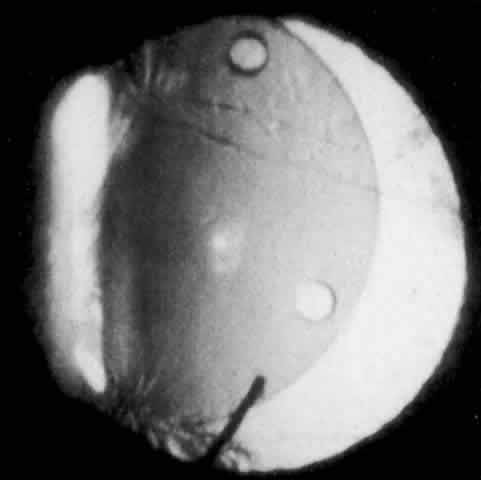

Cortical lens fragments retained in either the anterior chamber or the vitreous can also obstruct the trabecular meshwork in the form of free lens particles or macrophages swollen with lens material (Figs. 2 and 3). Glaucoma does not occur in all eyes that contain cortical remnants; the inflammatory response may be more pronounced and prolonged in eyes containing a higher amount of lens material. When inflammation is marked, keratic precipitates and sometimes a hypopyon may be present. Distinction between this sterile inflammatory endophthalmitis and infectious endophthalmitis can be difficult and may depend on the initial response to therapy. The presence or absence of IOP elevation is not helpful in making this distinction because IOP may be normal or elevated in both situations.